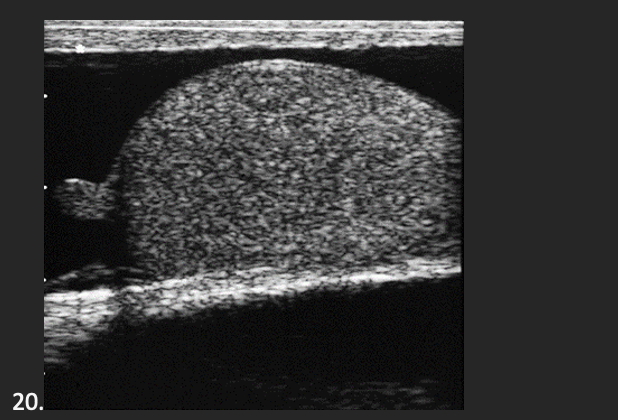

A 35 year old patient presents with a palpable scrotal mall. He is afebrile and denies any scrotal pain. This is most suspicious for what abnormality?

B. Testicular Torsion